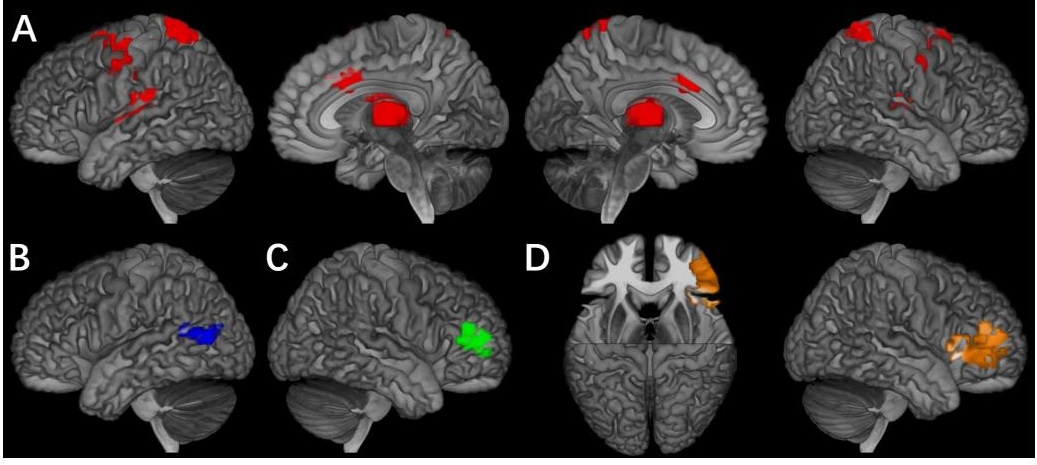

研究团队将“外向障碍”的症状分为四个行为域,即多动、冲动、注意力缺陷和品行问题,并找到其各自在奖赏预期和行为抑制任务中显著相关的核心脑区,这些行为域各自对应的核心脑区不仅在不同的行为域间具有显著的区别,并且指向了可能的共病机理。

图示:A)奖赏预期下的多动行为核心脑区;B)行为抑制任务下的冲动行为核心脑区;C)行为抑制任务下的注意力缺陷核心脑区;D)行为抑制任务下的品行问题的核心脑区。